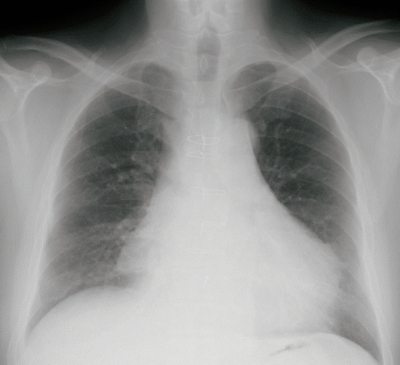

血液所見:赤血球 352万、Hb 10.7 g/dL、Ht 31%、白血球 8,700、血小板 10万。血液生化学所見:アルブミン 3.3 g/dL、総ビリルビン 1.2 mg/dL、AST 31 U/L、ALT 52 U/L、LD 331 U/L (基準 120~245) 、CK 50 U/L (基準 30~140)、尿素窒素 30 mg/dL、クレアチニン 1.1 mg/dL、Na 136 mEq/L、K 5.1 mEq/L、Cl 99 mEq/L。CRP 1.2 mg/dL。胸部エックス線写真及び胸部単純CTを別に示す。

症状に最も関連している病態はどれか。

e. 心嚢液貯留